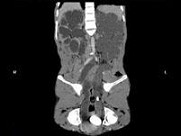

- 多项选择题男,33岁, 反复尿频,尿急, 尿痛3年余,排尿困难4月, 尿常规:蛋白(+), 红细胞0~1个/HP,白细胞(++), CT扫描如图所示,下列诊断哪项正确 ( )

A、膀胱结石

B、膀胱慢性炎性肉芽肿

C、膀胱癌

D、双侧肾积水,双侧输尿管扩张

E、膀胱多发性假性憩室